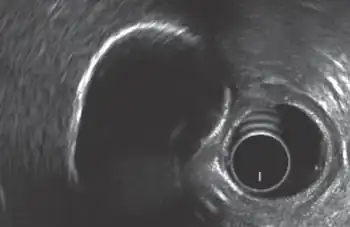

Porcelain gallbladder

Porcelain gallbladder is a calcification of the gallbladder believed to be brought on by excessive gallstones, although the exact cause is not clear. As with gallstone disease in general, this condition occurs predominantly in overweight female patients of middle age. It is a morphological variant of chronic cholecystitis. Inflammatory scarring of the wall, combined with dystrophic calcification within the wall transforms the gallbladder into a porcelain-like vessel. Removal of the gallbladder (cholecystectomy) is the recommended treatment.